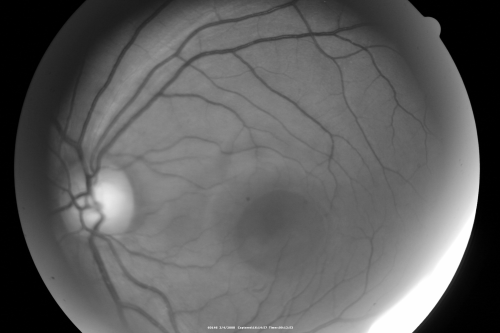

Central Serous Retinopathy

Red Free photo

Central Serous Retinopathy - Pinpoint Leak

37 year old man 20/25 vision